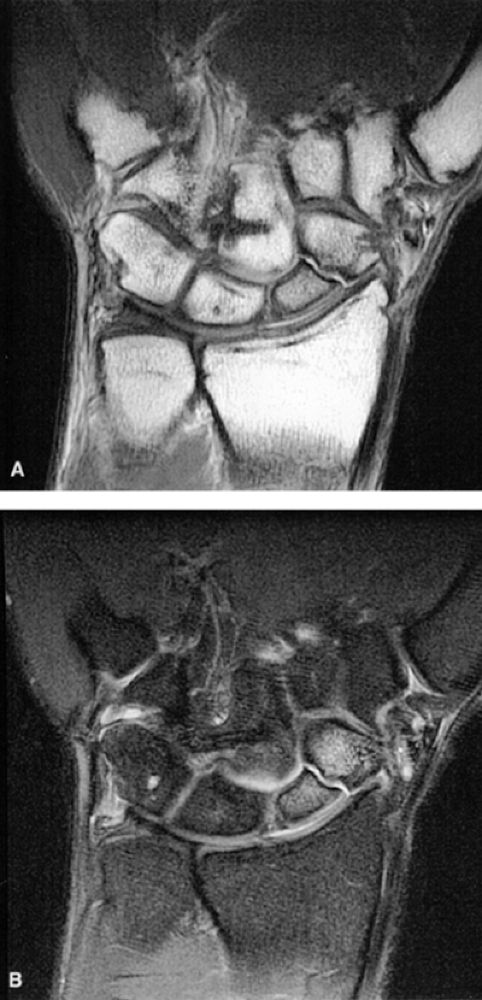

|